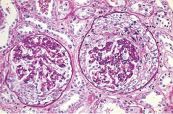

Cùng tìm hiểu về tìm kháng thể kháng màng đáy cầu thận bao gồm: nguyên nhân, nguy cơ, triệu chứng, cách chẩn đoán, để điều trị và kiểm soát bệnh hiệu quả nhất nhé